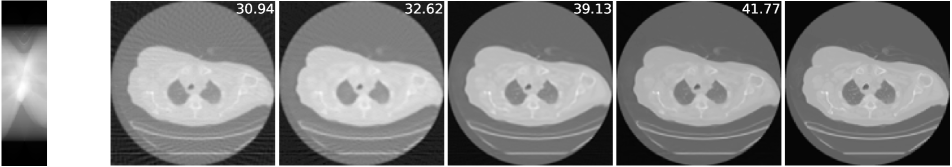

The imaging physics model of X-ray computed tomography (CT) is the discrete radon transform. The physics model is the radon transformation where 50 views (angles) are uniformly subsampled to generate the sparse-view sinograms (observations) . The Filtered back projection (FBP) function, i.e. iradon, is used to approximate . In this task, we exploit the invariance of the CT images to rotations222It is worth noting that shift invariance is not useful for the CT case, as the forward operator is shift invariant itself (see Corollary 1)., and is the group of rotations by degree (=360). We use the CT100 dataset [33], a public real CT clinic dataset which comprises 100 real in-vivo CT images collected from the cancer imaging archive333https://wiki.cancerimagingarchive.net/display/Public/TCGA-LUAD which consist of the middle slice of CT images taken from 69 different patients. The CT images are resized to pixels and we then apply the radon function on them to generate the -views sinograms. We used the first 90 sinograms for training while the remaining 10 sinograms for testing. Note in this task, the supervised trained residual U-Net is just the FBPConvNet proposed in [12] which has been demonstrated to be very effective in supervised learning for sparse-view CT image reconstruction. We train our model with equivariance strength (see SM for more results and the equivariance strength effect). using the sinograms alone while the FBPConvNet is trained with the ground truth pairs .

A qualitative comparison is presented in Figure 4. The sparse-view FBP contains the line artifacts. Both the FBPConvNet and our methods significantly reduce these artifacts, giving visually indistinguishable results. Figure 5 shows the value of PSNR of reconstruction on the training measurements and test measurements and we have the following observations: (i) We would naturally expect the network trained with ground truth data to perform the best. However, we note that the equivariant test error is almost as good despite having no access to ground truth images and only learning on the sparse sinogram data. Furthermore the EI solution is about 7 dB better than the FBP, clearly demonstrating the correct learning of the null space component of the image. (ii) We note that there is a significant gap between training and test error for the FBPConvNet, suggesting that the network may be overfitting. We do not observe this in the EI learning. This can be explained by the fact that the EI constrains the network to a much small class of functions (those that are equivariant on the data) and thus can be expected to have better generalization properties.

We also compared the EI with its adversarial extension in (7) and the supervised learning regularized by equivariance objective. The quantitative results are given in table 1 below. First, MC learning obtains a small improvement in performance over FBP which may be attributable to the fact that FBP is only an approximation to . Alternatively it may be due to the inductive bias of the neural network architecture [34]. Second, the adversarial extension provides a slight improvement to EI and similarly the EI regularization helps the vanilla supervised learning obtain a further 0.6 dB improvement. These results suggest that it is indeed possible to learn to reconstruct challenging inverse problems with only access to measurement data.

| FBP | MC | EI | Sup | |||

|---|---|---|---|---|---|---|

| 50-views CT | 30.24 | 31.01 | 36.94 | 36.96 | 38.17 | 38.79 |